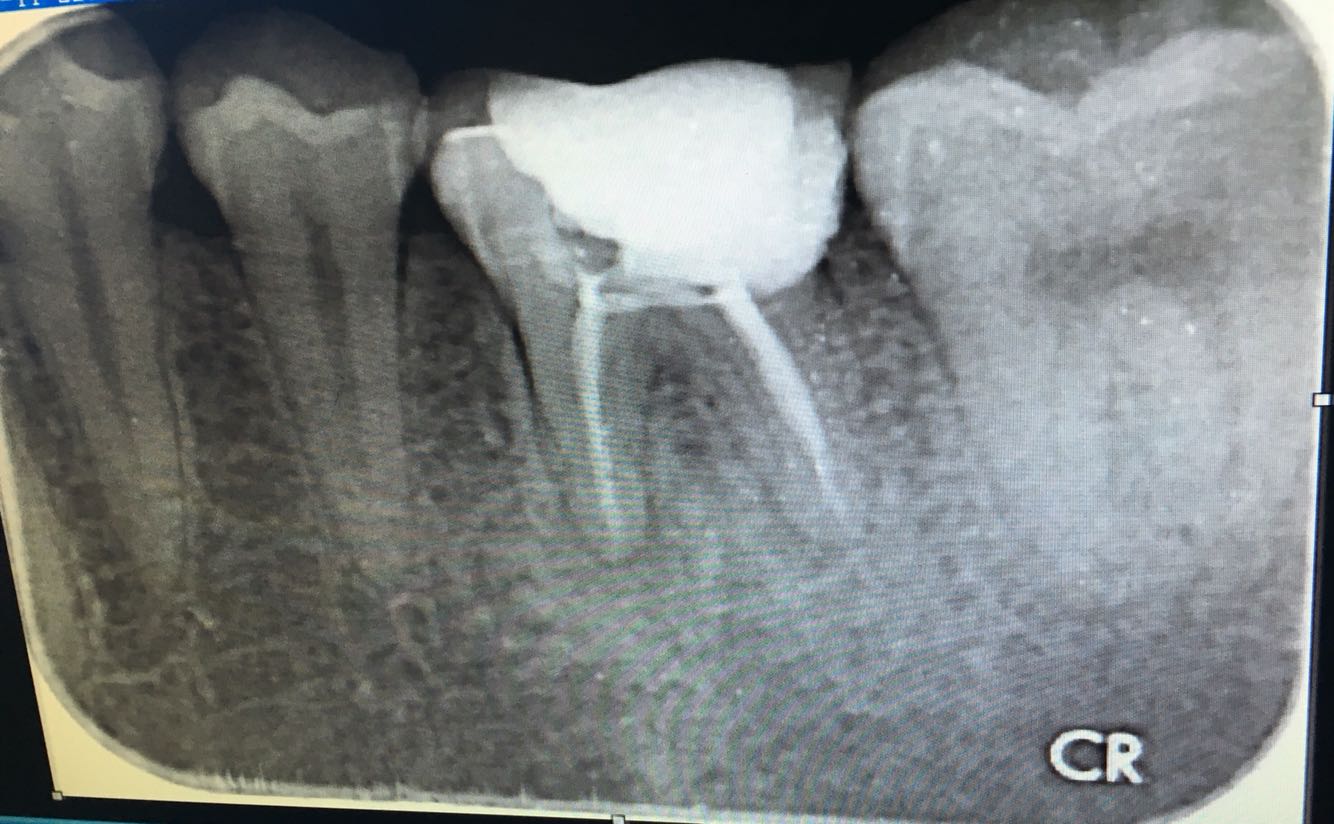

诊断:26冠折,26慢性牙髓炎 (欠填) 治疗计划:26拔除松动残片,26根管再治疗术.术后高嵌体修复  处置: 26局麻下拔除松动残片,去除原表面暂充填物,丁克除去除远中根管内牙胶尖,疏通根管,电测根长,17mm,.近颊根管疏通,电测17.5mm,EDTA扩大至30#,3%双氧水+0.9% 生理盐水交替冲洗,拭干,根管糊剂+牙胶尖冷侧压法根充,氧化锌粘固粉暂 封。X-ray 示:26根充完好。建议1周后无症状高嵌体修复,常规医嘱。

患牙两年前根管治疗,远中根欠充,近颊根管遗漏,根尖片示根尖区无异常,牙体叩痛无,但是想要进行修复治疗牙体治疗必须完善了,所以与患者沟通,此牙进行根管再治疗,观察两周后进行修复术